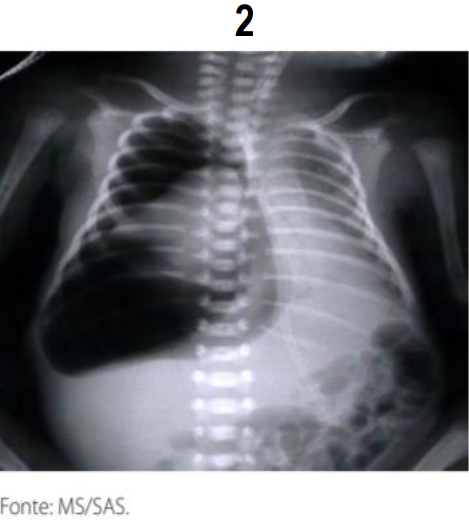

A radiografia de tórax é o exame de eleição para o diagnóstico das várias formas de SEAr. É fundamental, também, para a determinação do tamanho e da extensão da coleção de ar e da coexistência de outras entidades que possam facilitar ou perpetuar o escape de ar, além de permitir o acompanhamento evolutivo e avaliar a eficácia da terapêutica adotada. Na grande maioria dos casos o aspecto radiológico é típico, sendo possível definir o diagnóstico com relativa facilidade. Analise as imagens radiológicas com sinais patognomônico e assinale a alternativa da doença associada